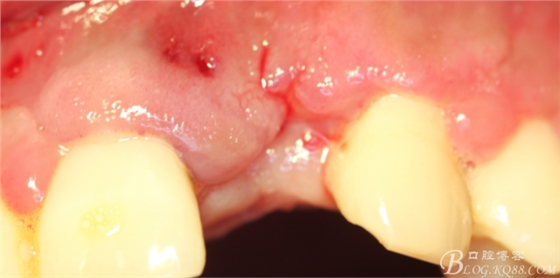

10天拆線一切正常,又過了兩周患者復(fù)診,自述期間無異常??趦?nèi)檢查,真的嚇了一跳,唇側(cè)鼓了個(gè)包,擠壓有白色分泌物溢出,絕對不是膿液,液體排除后,術(shù)區(qū)觸診空虛,外觀塌陷。這時(shí)候考研大夫的時(shí)刻到了,是先觀察一段時(shí)間再說?還是馬上進(jìn)行處理?我的回答是:馬上處理!如果你沒有及時(shí)處理,而是放患者回家觀察,那么接下來會(huì)發(fā)生如下情況:1.回家后患者家屬及親友會(huì)有很多你可以想象得到的討論;2.患者及家屬會(huì)對你產(chǎn)生不信任,勢必會(huì)到其他門診或醫(yī)院檢查,他院大夫會(huì)不會(huì)發(fā)表對你不利的言論;3甚至?xí)蚁嚓P(guān)法律界人士找你討要說法。

于是我果斷告知患者,手術(shù)失敗了,不能拖延,如不及時(shí)處理,炎癥繼續(xù)發(fā)展會(huì)很快波及鄰牙牙槽骨。患者接受我的建議。切開翻瓣,骨粉及生物膜消失了,骨吸收嚴(yán)重,幸運(yùn)的是,因?yàn)樘幚砑皶r(shí),鄰牙骨支持依然存在。